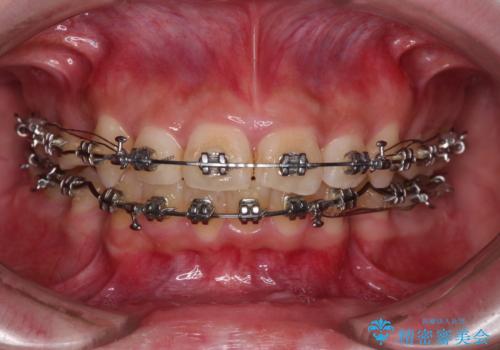

- 矯正装置

- メタルブラケット

- 治療期間

- 2年6ヶ月

下顎骨の左右差や、上顎骨の前方位などが認められたため、上下左右の第1小臼歯4本を抜歯し、ワイヤー装置にて矯正治療を行うこととしました。